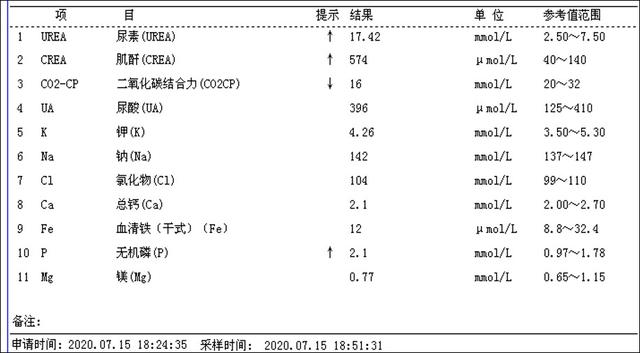

介入微创消融治疗后第一天甲状腺旁腺素降为486.2pg/ml(治疗前为3300pg/ml),静脉持续补钙血钙正常